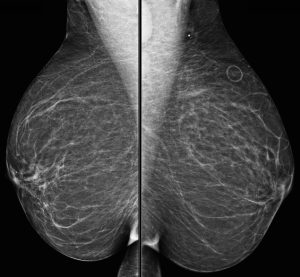

A 71-year-old woman presents with a palpable lump. A BB skin marker is placed over the area of concern and a diagnostic mammogram is performed.

Explanation: The metallic BB marker overlies the axilla and is only seen on the MLO projection. On that image, we see a definitely enlarged lymph node and a second lymph node inferiorly that is also probably enlarged.